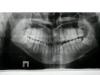

Сергей Поддубнов Опубликовано 14 сентября, 2010 Поделиться Опубликовано 14 сентября, 2010 Добрый день форумчане! Мне 23 года. У меня такая проблема - верхняя челюсть уже нижней, из-за этого проблемы с жеванием и смыканием зубов + мезиальный прикус. Подскажите пожалуйста, какое лечение мне подойдет? В нашем городе врачей, занимающихся хирургической стоматологией нет, по-этому обратиться за помощью не кому(( Вот фото Ссылка на комментарий